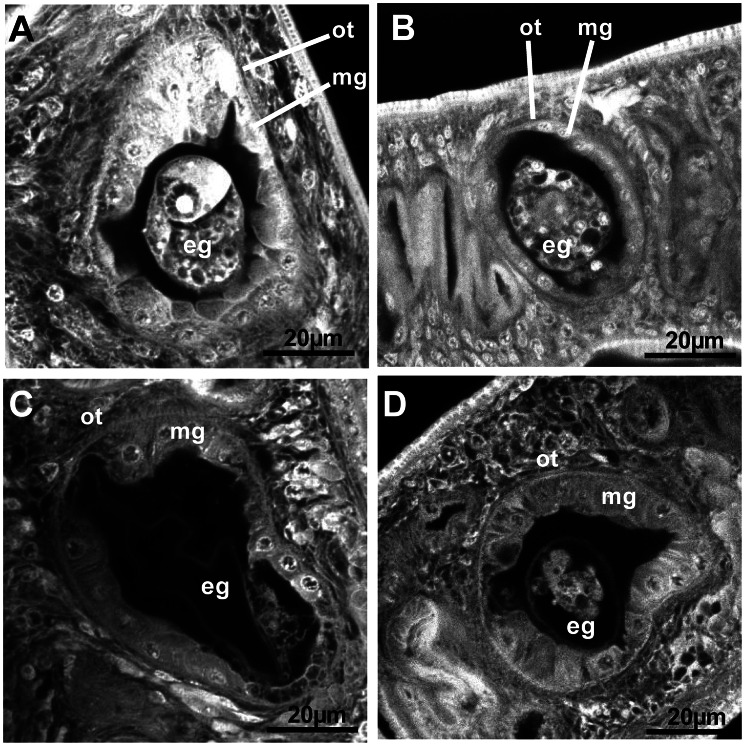

Chemotherapy of schistosomiasis relies on a single drug, Praziquantel (PZQ) and mass-use of this compound has led to emergence of resistant strains of Schistosoma mansoni, therefore pointing out the necessity to find alternative drugs. Through their essential functions in development and metabolism, receptor tyrosine kinases (RTK) could represent valuable drug targets for novel anti-schistosome chemotherapies. Taking advantage of the similarity between the catalytic domains of S. mansoni insulin receptors (SmIR1 and SmIR2) and Venus Kinase Receptors (SmVKR1 and SmVKR2), we studied the possibility to fight schistosomes by targeting simultaneously the four receptors with a single drug.Several commercial RTK inhibitors were tested for their potential to inhibit the kinase activities of SmIR1, SmIR2, SmVKR1 and SmVKR2 intracellular domains (ICD) expressed in Xenopus oocytes. We measured the inhibitory effect of chemicals on meiosis resumption induced by the active ICD of the schistosome kinases in oocytes. The IR inhibitor, tyrphostin AG1024, was the most potent inhibitory compound towards SmIR and SmVKR kinases. In vitro studies then allowed us to show that AG1024 affected the viability of both schistosomula and adult worms of S. mansoni. At micromolar doses, AG1024 induced apoptosis and caused schistosomula death in a dose-dependent manner. In adult worms, AG1024 provoked alterations of reproductive organs, as observed by confocal laser scanner microscopy. With 5 µM AG1024, parasites were no more feeding and laying eggs, and they died within 48 h with 10 µM.IRs and VKRs are essential in S. mansoni for key biological processes including glucose uptake, metabolism and reproduction. Our results demonstrate that inhibiting the kinase potential and function of these receptors by a single chemical compound AG1024 at low concentrations, leads to death of schistosomula and adult worms. Thus, AG1024 represents a valuable hit compound for further design of anti-kinase drugs applicable to anti-schistosome chemotherapy.